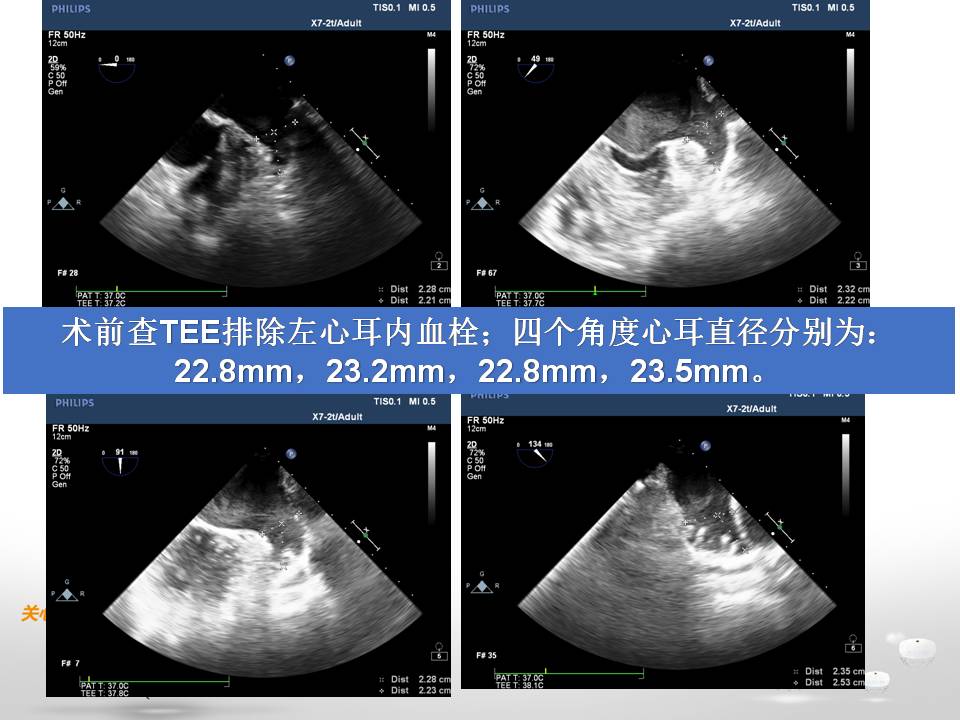

tee左心耳血栓

图片尺寸1920x1080